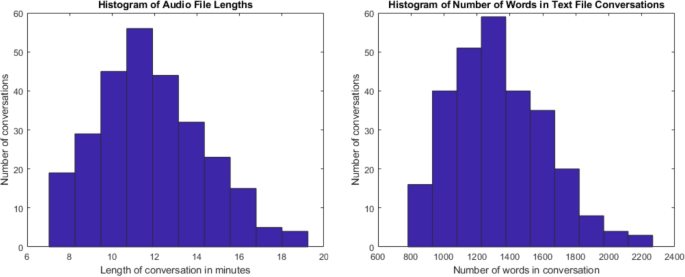

272 cases were simulated and recorded (please refer to Fig. 1 ). The focus of the dataset was respiratory cases (214 cases). In addition, 46 musculoskeletal cases, 5 cardiac cases, 6 gastrointestinal cases and 1 dermatology case were also simulated. Of the total simulated recordings, 57% of the cases involved a male physician and 43% involved a female physician. From the patient perspective, 55% of the simulated cases involved a male patient and 45% involved a female patient. The average duration of each conversation was 11 minutes and 56 seconds. For further details, please refer to Fig. 2 for a histogram of the number of cases corresponding to various lengths of time. The focus was on respiratory cases because most pandemics, including the COVID19 pandemic, are caused by droplet or airborne based respiratory diseases. Therefore, it is crucial to differentiate between a benign cause of malaise such as the common cold from a highly infectious and fatal cause such as COVID19 or Tuberculosis.

Histograms displaying the number of conversations with their corresponding length of time in minutes (left) and number of words per conversation (right).